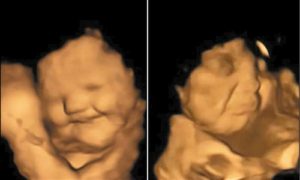

அதில் கேரட் கேப்சூல் விழுங்கிய கர்ப்பிணிகளின் கருக்குழந்தைகள் புன்னகைப்பதையும், பரட்டைக்கீரை கேப்சூலை சாப்பிட்ட கர்ப்பிணிகளின் கருக்குழந்தைகள் சிணுங்கி அழுவதுபோல காணப்படுவதையும் கண்டுபிடித்தனர். அதாவது, கேரட் கருக்குழந்தைகளுக்கு பிடித்து, அவர்களைப் புன்னகைக்க வைத்திருக்கிறது. பரட்டைக்கீரை அவர்களை சிணுங்க வைத்திருக்கிறது. கவனியுங்கள். இதில் கருக்குழந்தைகள் எதையும் சாப்பிடவில்லை. அவர்களின் தாய்கள்தான் அவற்றை சாப்பிட்டு இருக்கிறார்கள்.

இதுபற்றி ஆராய்ச்சியாளர்கள் மேலும் கூறும்போது, “கேரட் சுவை வெளிப்படும்போது கருக்குழந்தைகள் சிரிப்பு முகம் காட்டவும், பரட்டைக்கீரை சுவை வெளிப்படும்போது, அவை சிணுங்கும் அழுகை முகம் காட்டவும் அதிக வாய்ப்பு உள்ளது. பல்வேறு சுவைகளை உணரவும், பாகுபடுத்தவும் கருக்குழந்தைகளின் திறன்களின் ஆரம்ப கால ஆதாரங்களை புரிந்து கொள்வதற்கு இந்த ஆராய்ச்சிகள் முக்கிய தாக்கங்களை கொண்டுள்ளன” என தெரிவித்தனர்.